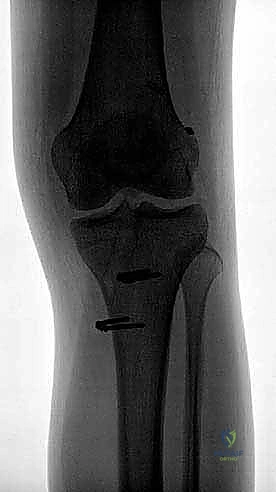

هنا تكمن الصعوبة والتميز في تقنية الحزمتين. بدلاً من حفر نفق واحد في الساق ونفق في الفخذ، يقوم الدكتور هطيف بحفر أربعة أنفاق دقيقة:

* نفقان في عظم الظنبوب (الساق): يتم تحديد البصمة التشريحية الأصلية لحزمة AM وحزمة PL بدقة متناهية، ويتم حفر نفقين منفصلين.

* نفقان في عظم الفخذ: باستخدام أدوات توجيه خاصة ورؤية المنظار الدقيقة، يتم حفر نفقين في موقع المنشأ الأصلي لكل حزمة على جدار الفخذ.

- اللحظة الحاسمة (تطبيق التوتر الديناميكي): لا يتم تثبيت الأوتار في عظم الساق عشوائياً. يقوم الدكتور هطيف بشد وتثبيت حزمة (AM) بينما الركبة مثنية بزاوية تتراوح بين 45 إلى 60 درجة. ثم يقوم بشد وتثبيت حزمة (PL) بينما الركبة في حالة تمدد شبه كامل (زاوية 10-15 درجة). هذه الخطوة العبقرية هي التي تعيد الميكانيكا الحيوية الطبيعية للركبة. يتم التثبيت النهائي في الساق باستخدام براغي تداخلية قابلة للامتصاص (Bio-absorbable Screws).